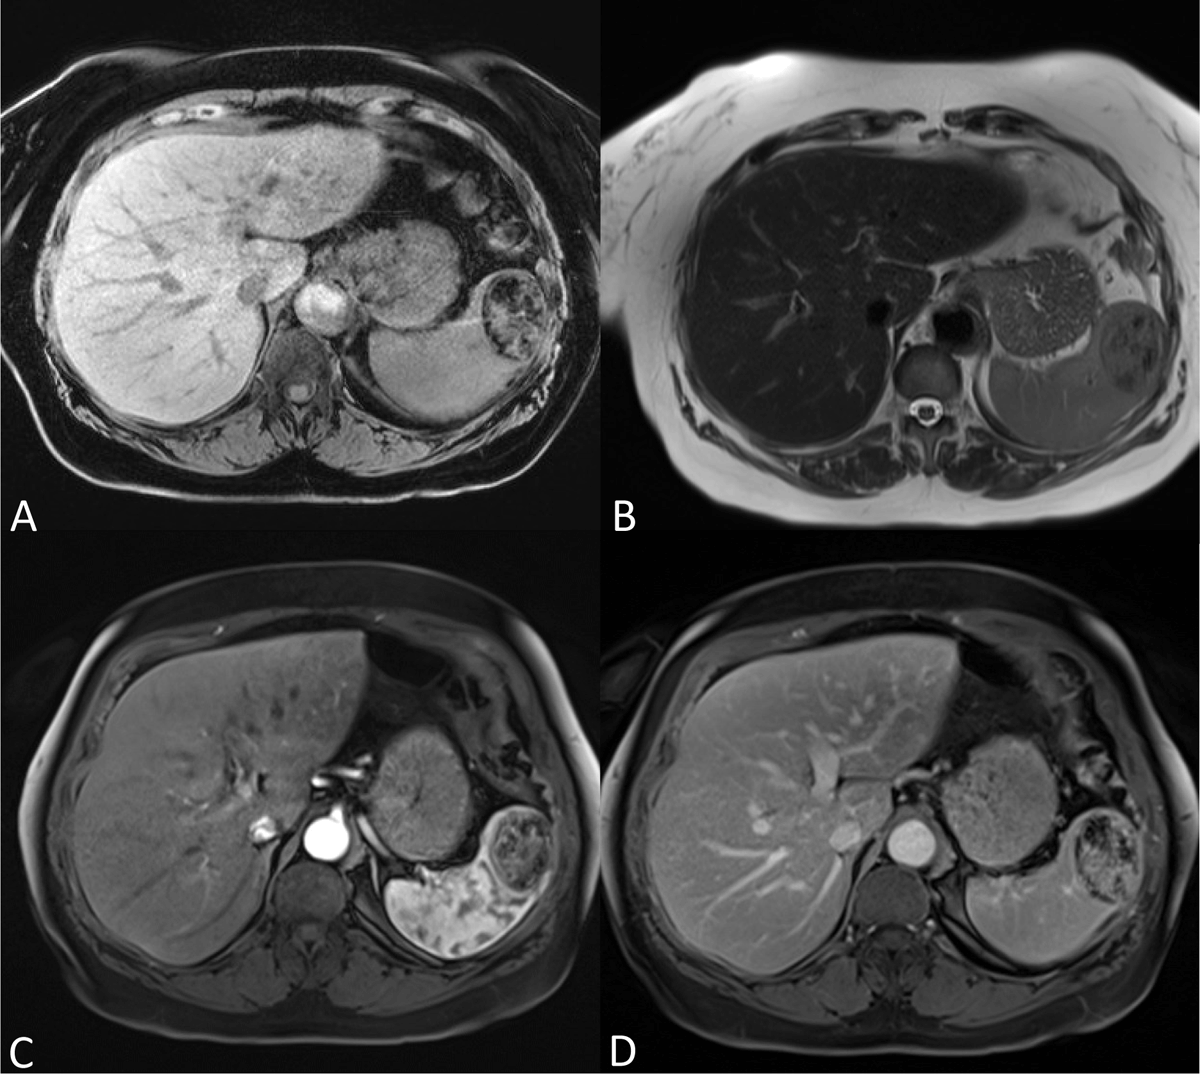

Figure 2

(A) Unenhanced axial fat suppressed T1-weighted imaging shows the lesion is sharply delineated with abundant hypointense foci. (B) Axial T2-weighted imaging shows a sharply delineated heterogeneous mass with both iso- and hypointense components. (C–D) Axial fat suppressed T1-weighted imaging after injection of gadolinium contrast shows a relative heterogeneous and weak enhancement in the arterial phase progressively filling in at the delayed phase, although remaining heterogeneous. No central scar or spoke-wheel enhancement pattern was present.